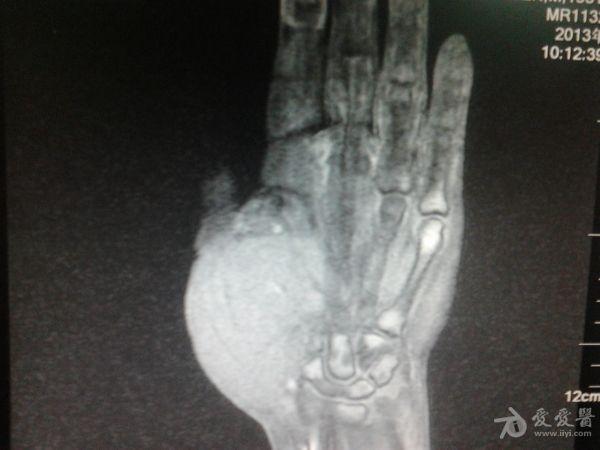

右第一掌骨、大多角骨肿瘤

男性患者,81岁,右手肿痛3个多月。无任何其它症状。体查:右手第一掌骨部肿胀明显,第一指活动受限,余四指活动可,腕关节活动小部分受限,活动时会痛。影像学检查如下。活检示:弥漫性大B细胞淋巴瘤。大家看看需不需要截肢?现在有人主张手术;有人主张不手术,直接化疗。大家有什么看法?